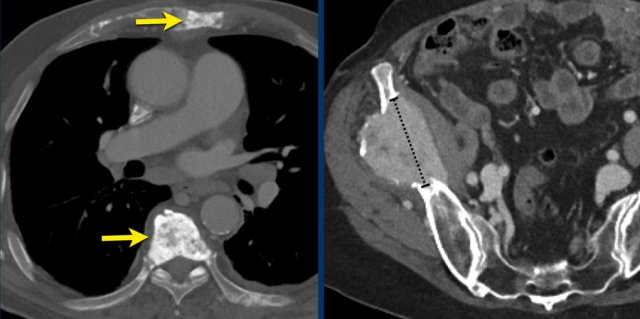

Bone metastases

During follow-up bone metastases quite often change in appearance while the size remains the same, therefore they are generally considered non-measurable lesions.

According to RECIST 1.1. only lytic or mixed lytic-blastic bone metastases with identifiable soft tissue component can be considered as measurable lesions if they meet the measurability criteria.

The left CT image is of a 80-year-old male with osteoblastic bone metastases of a non-small-cell lung carcinoma.

This lesion is not suitable for measurement.

The CT image on the right is of a 69-year-old female with an osteolytic metastasis in the right iliac bone.

This metastasis is suitable for measurement and can be used as target lesion.

Sometimes the largest lesion is not the most suitable for reproducible repeated measurements.

This CT image is of a 61-year-old male with gastric cancer and lymph node metastases.

There is a large lobulated mobile gastric tumor.

We can assume, that on a follow up examination it can not be reproduced in the same way.

Therefore this mobile tumor is not suitable as target lesion, but can be used as non-target lesion.

Continue with next image...

At a lower level there is an enlarged lymph node which is more suitable to be used a target lesion (arrow).